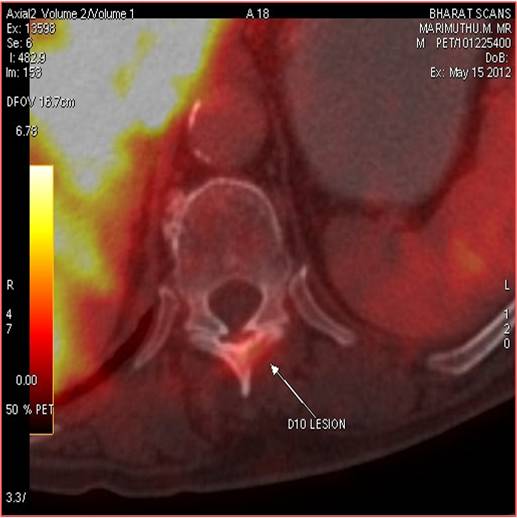

CT scan of the abdomen confirmed the findings ; For further clarification PET whole body scan was done at a centre in Chennai. The following images are from that.

Focal FDG avid lesion in left lamina of D10 – possibly metastatic.